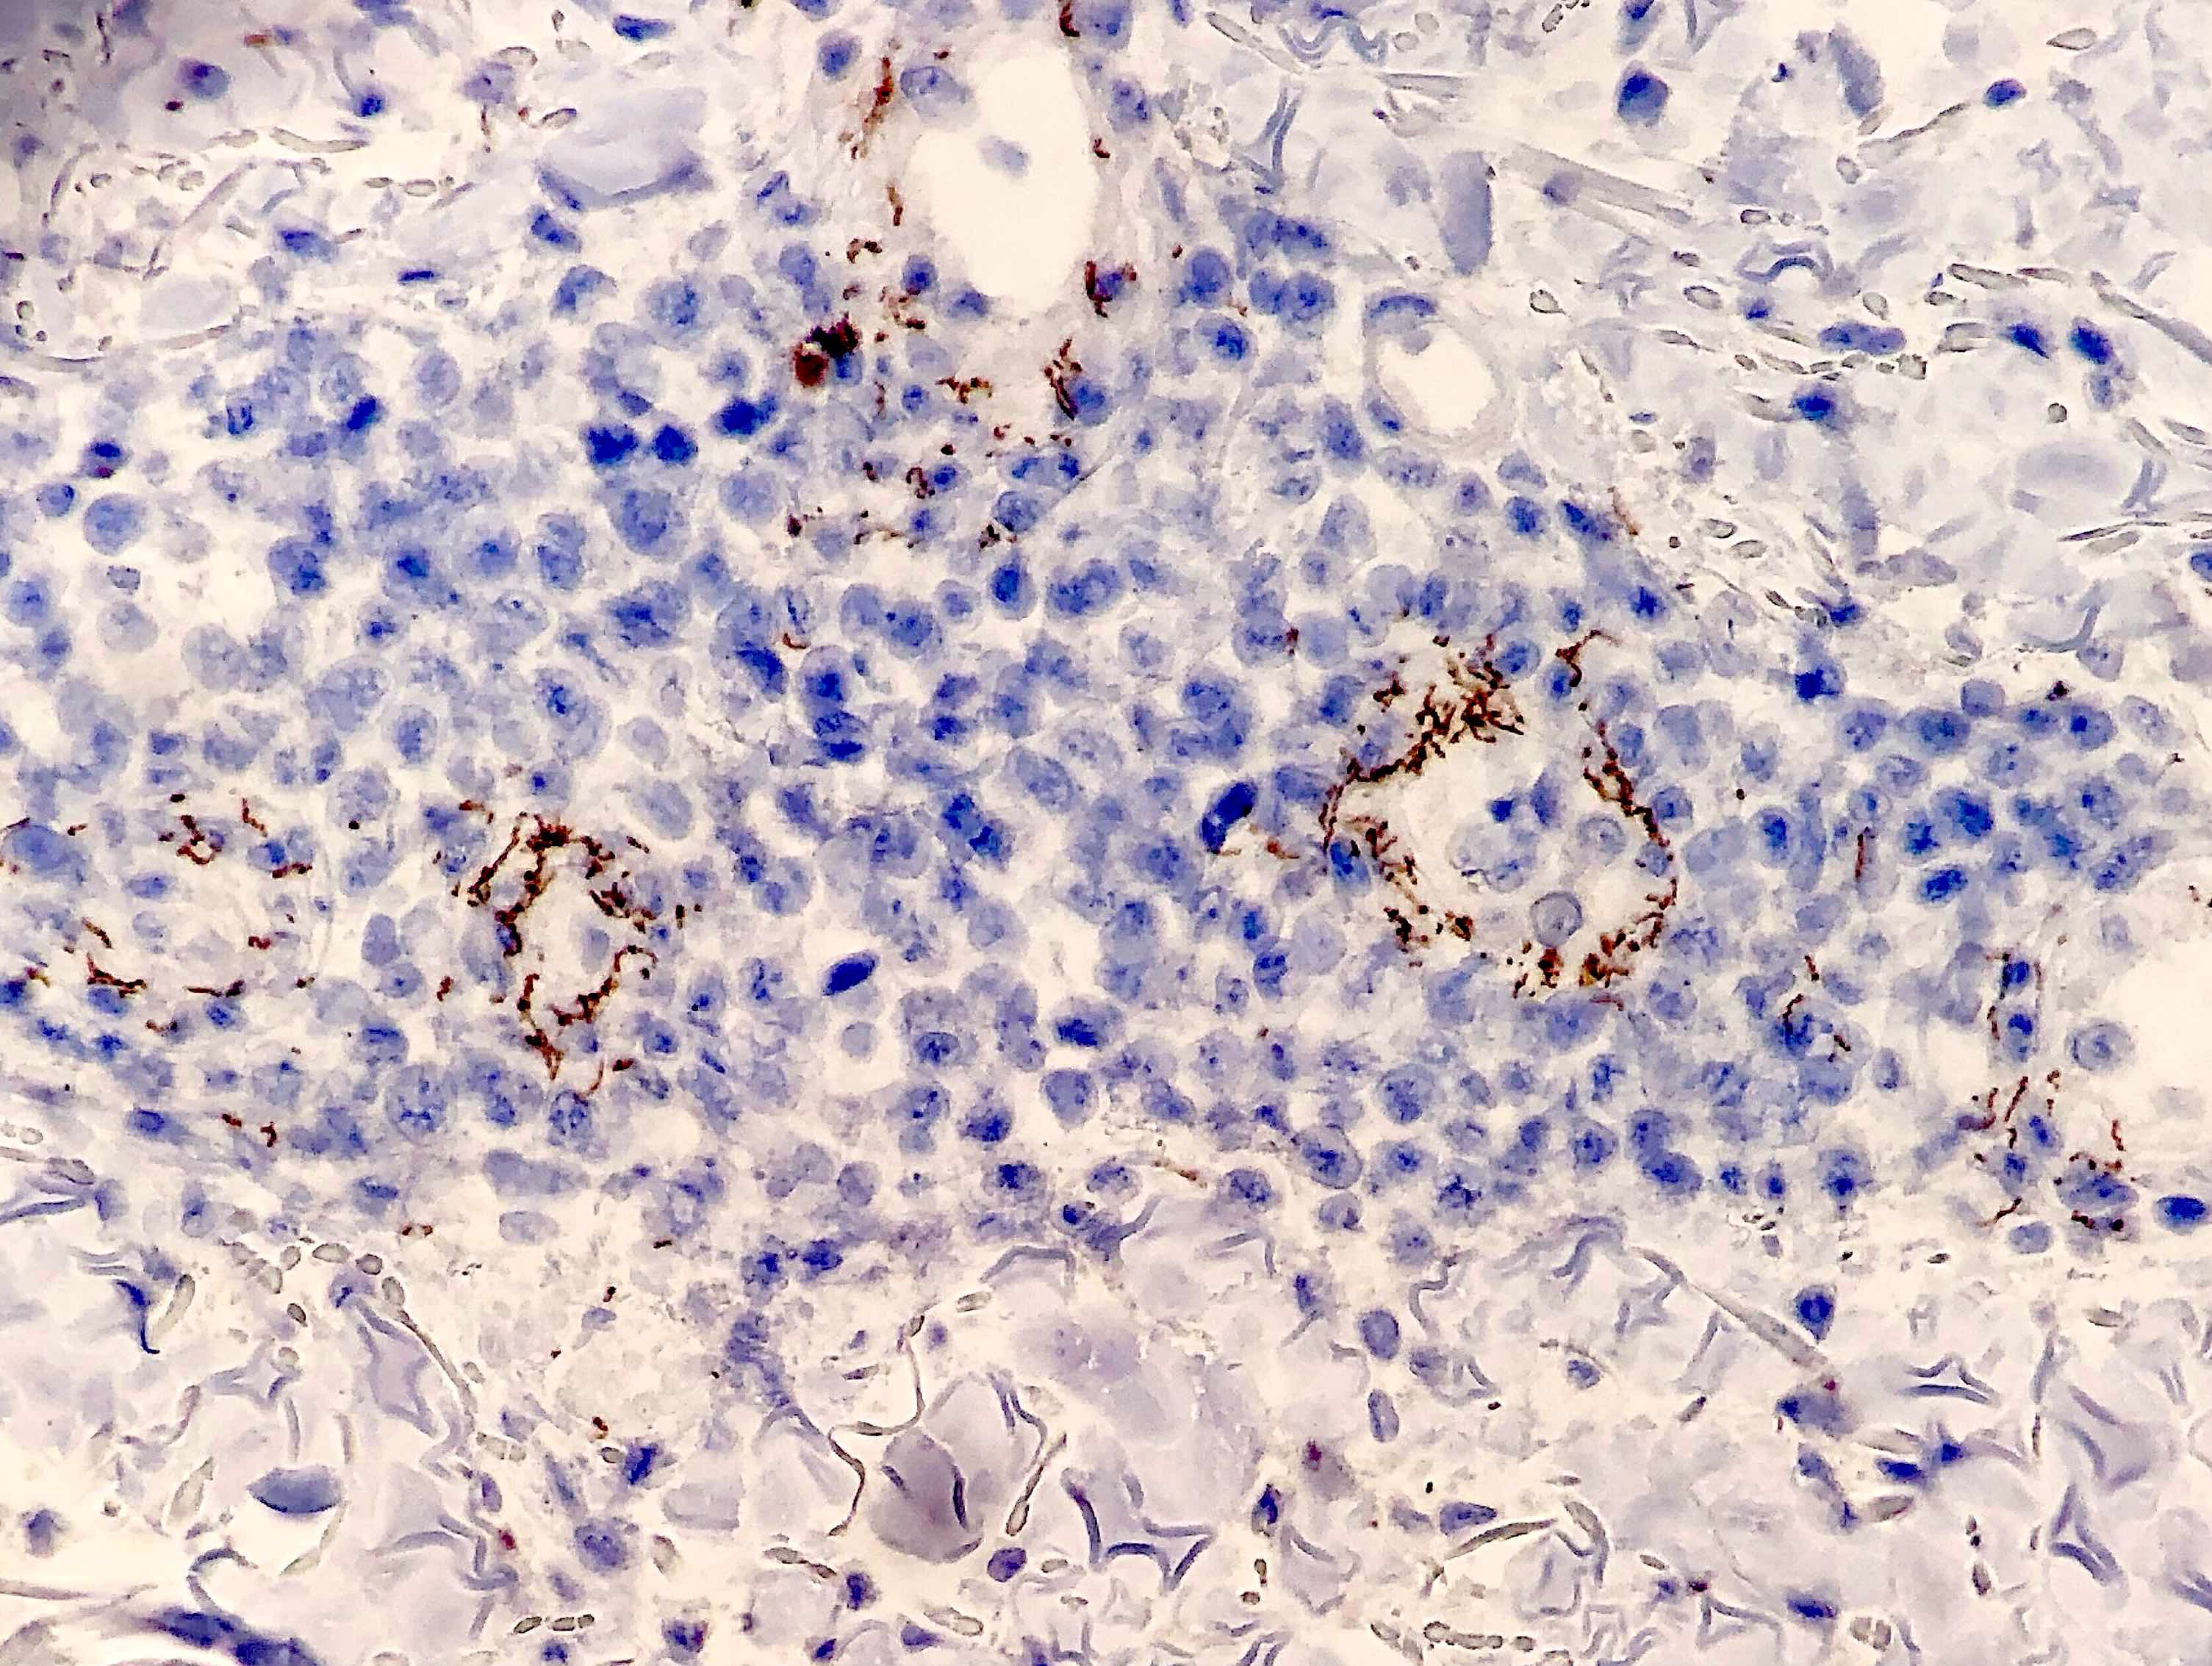

Microscopic (histologic) images

Contributed by Silvija P. Gottesman, M.D., Hillary Rose Elwood, M.D., Mark R. Wick, M.D. and AFIP images

Positive stains

- Silver stains: Warthin-Starry or Steiner stain (41% sensitive) (J Cutan Pathol 2004;31:595)

- Immunohistochemical stain: treponema (71% sensitive) (J Cutan Pathol 2004;31:595)

- Lymph node:

- Primary syphilis:

- Capsular and pericapsular fibrosis, follicular hyperplasia, diffuse interfollicular plasma cells, prominent endarteritis outside the capsule

- Noncaseating granulomas and abscesses are rare

- Spirochetes easiest to identify within blood vessel walls